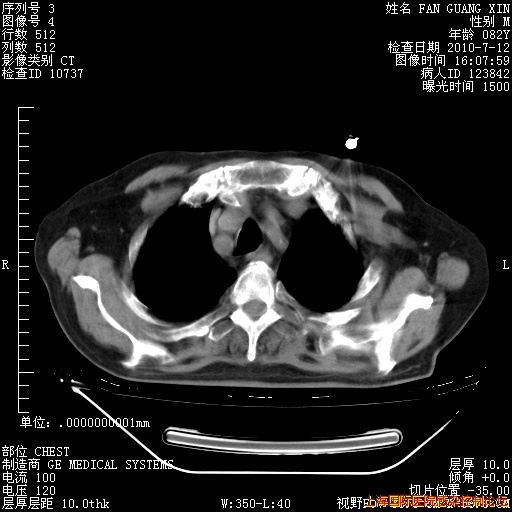

今天CT